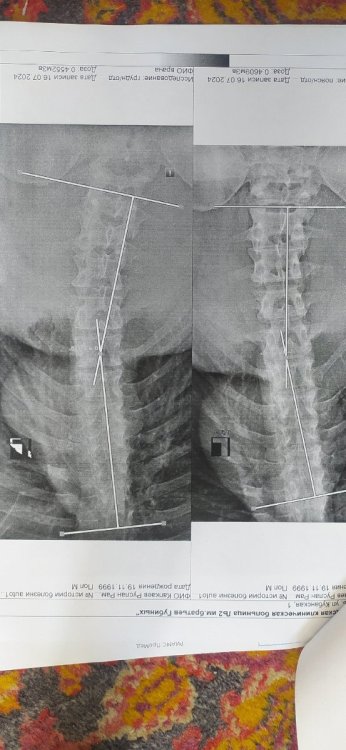

Первоначально при обследовании сколиоза посчитали 20 градусов и поставили В в местном военкомате. Затем в областном военкомате категорию не подтвердили и отправили на новое обследование в другую больницу. Ниже прикрепляю медицинское заключение уже из новой больницы ( тут насчитали 17.7 градусов ). Могу ли я претендовать на категорию В ?

p_MxqC4Z0NM.jpg

sAQYlSYIhzA.jpg